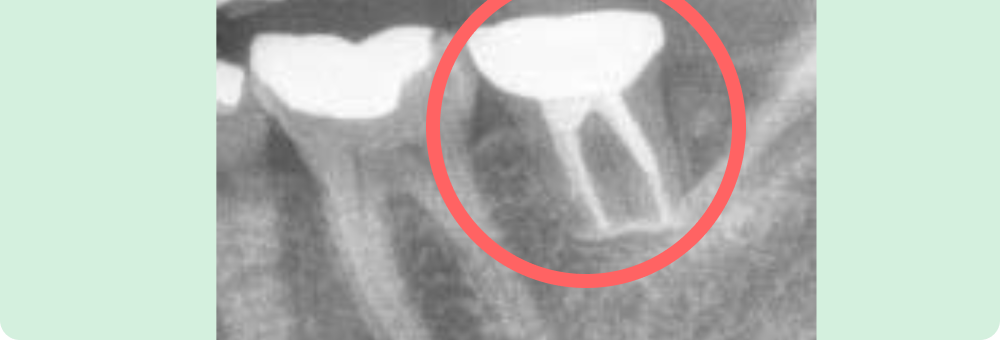

右下奥歯の移植

右下の一番奥の歯が破折し、保存が難しい状況でしたので抜歯し、同時に右下奥の親知らずを抜いて手前に移植しました。

現在もしっかり機能してます。

主訴

右下奥歯が痛い

患者様

40代/女性

治療期間

4ヶ月

費用

約20,000円(税込)保険内